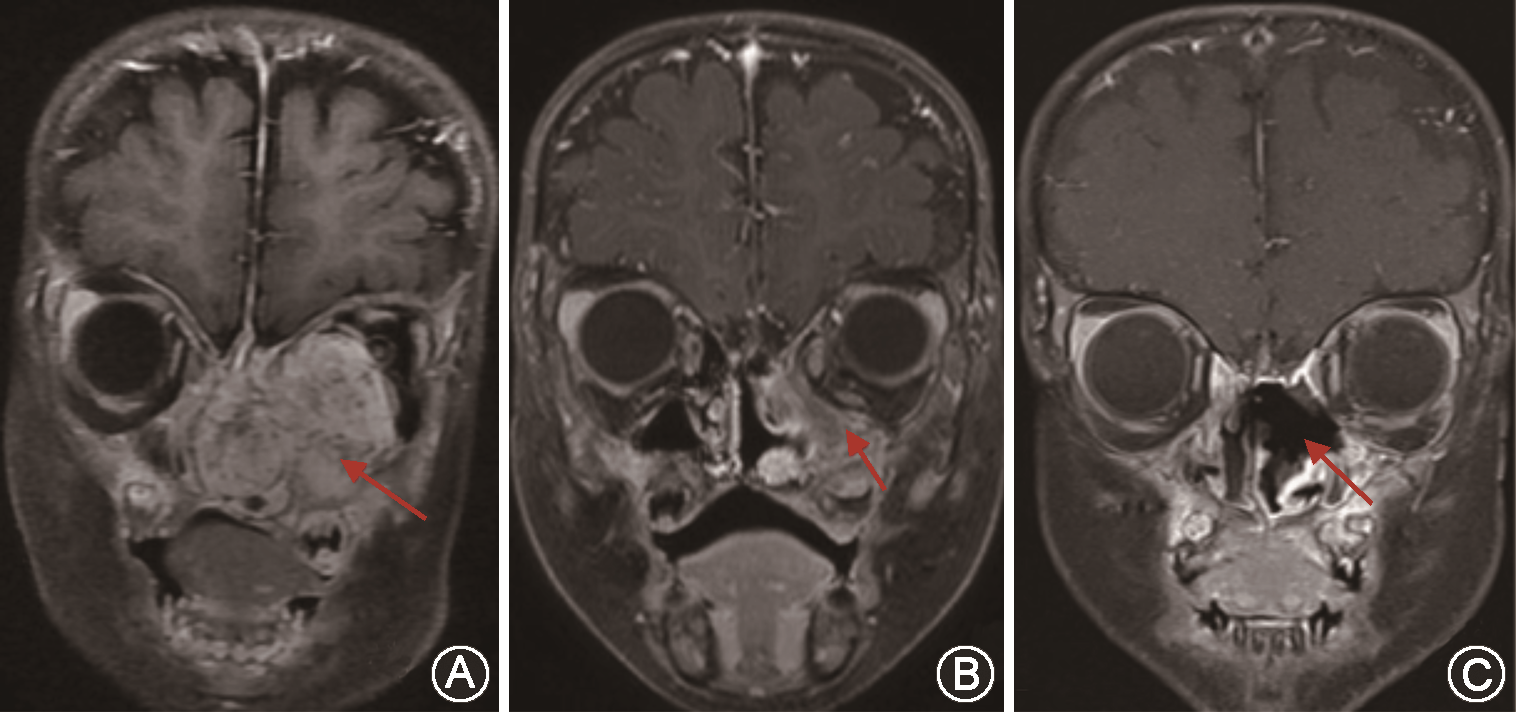

入院后行头颅增强MRI提示:肿物累及双侧鼻腔、鼻窦、前颅底,左侧视神经受压变窄并稍向外移位,左侧海绵窦、前颅窝底硬脑膜受侵(图2A)。PET-CT提示:鼻腔巨大肿块、代谢活跃,肿瘤突入前颅窝底及左侧眼眶,侵犯双侧上颌骨、蝶窦、筛窦、筛骨及蝶骨、左侧颞骨(图3A),双侧咽旁间隙及双侧颈Ⅱ区、左颈Ⅰ区多发代谢活跃淋巴结,考虑转移瘤可能性大(图3B)。左眼内直肌、下直肌、视神经受压;余全身未见转移征象。血红蛋白浓度81.00 g/L,甲胎蛋白(AFP)43 230.5 ng/ml。中山大学附属第三医院病理科会诊外院病理切片,加做免疫组化后提示:核分裂相易见,瘤细胞排列呈网状、管囊状、乳头状及小管状,可见嗜酸性玻璃样小体,结合免疫组化结果,符合卵黄囊瘤(图4A)。

患儿入院后经病理科、影像科、核医学科、儿科、神经外科多学科会诊后认为:目前肿瘤巨大,突入前颅窝底及左侧眼眶,且视神经受压。属于卵黄囊瘤Ⅳ期,并且中枢神经系统侵犯,肿瘤完整切除难度较大,手术治疗极易出现颅脑及眶内并发症,大大降低患儿生存质量。可先行术前化疗,待肿瘤范围缩小后,争取手术时机。遂转入儿科行PEB方案(顺铂、依托泊苷、博来霉素)先后进行6个疗程化疗,第3个疗程结束后患儿AFP降至正常水平。3个疗程后患儿左眼球前突明显好转(图1B),头颅增强磁共振扫描显示肿瘤较前明显缩小(图2B)。PET-CT提示:原鼻腔肿物较前明显缩小,大部分区域代谢恢复正常(图3C)。双侧颈Ⅱ区、左颈Ⅰ区淋巴结代谢较前降低,部分恢复正常(图3D)。遂转入我科全麻下采用神经手术导航系统经鼻内镜下左侧颅底肿瘤切除、鼻窦开放术,术中见瘤体主要位于翼腭窝,上至眶底、眶内侧及前颅底,下至总鼻道,内至鼻中隔、蝶窦腔,外至翼腭窝、颞下窝,经翼内肌、翼外肌内侧至蝶窦及斜坡前方。病变区域为大量机化组织及粗糙骨小梁样物,切除前颅底病变并磨除部分骨质直至显露正常骨质,沿眶筋膜层面将肿瘤组织连同眶纸板一并切除。经后囟进入翼腭窝,经导航定位肿瘤外侧界后,将瘤体整体分离,见边界尚清,未损及颌内动脉。至此,瘤体完整切除,标本送病理检查。术中出血约200 ml,输血RBC 1 U。